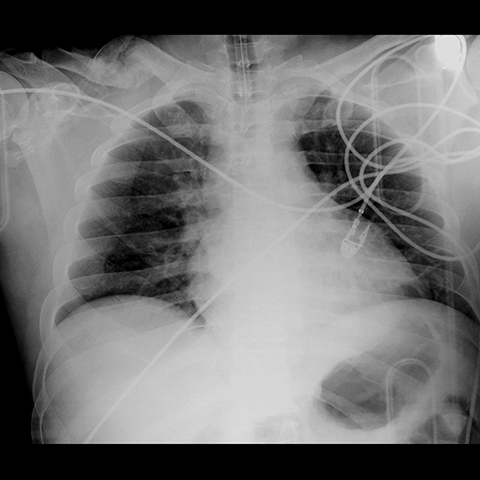

Portable AP Chest Radiograph [3 of 3]

Lines

Lines and Labels